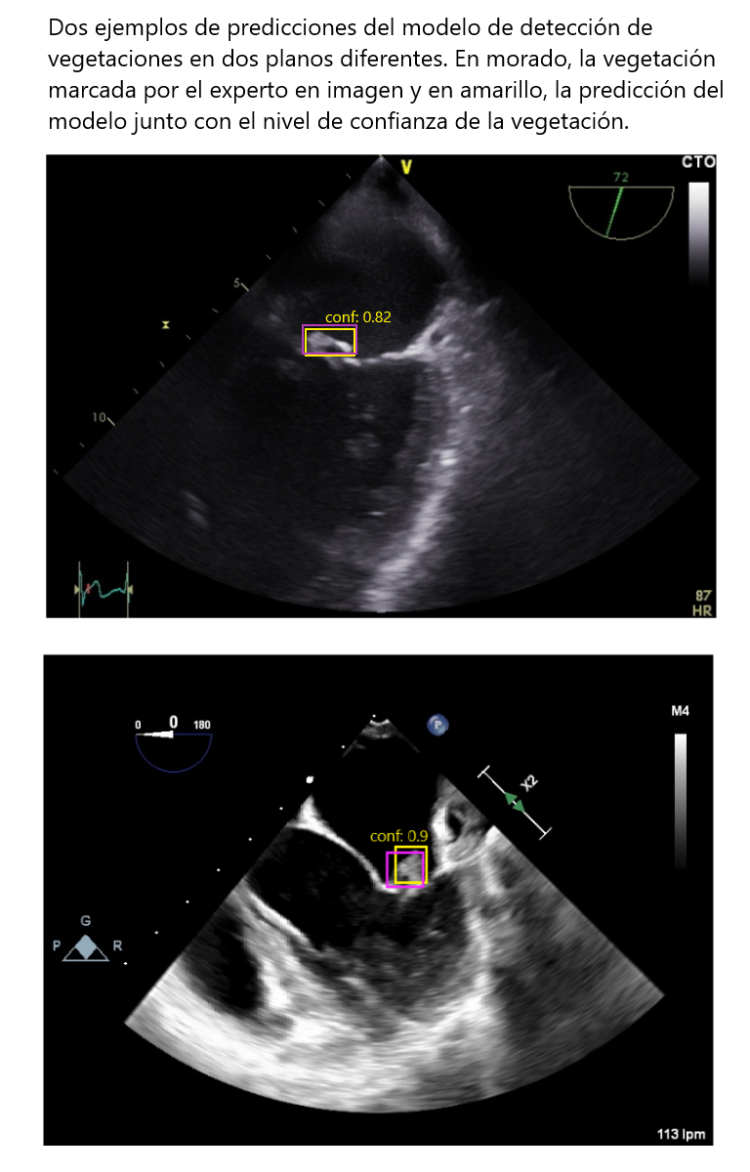

Ejemplos de predicción del modelo de IA.

Resultados: En la primera fase, el modelo alcanzó métricas prometedoras con una precisión de 0,81 y una sensibilidad de 0,72 para la detección de vegetaciones en imágenes. En la segunda fase, la validación clínica demostró una sólida capacidad diagnóstica del modelo para identificar pacientes con vegetaciones al analizar secuencias completas de video, con un área bajo la curva (AUC) de la característica operativa del receptor (ROC) de 0,92.

Métodos: Estudio observacional retrospectivo realizado en 7 hospitales, dividido en dos fases. En la primera fase, se anotaron manualmente datos de 203 pacientes, los cuales se utilizaron para entrenar un modelo de IA capaz de recibir una imagen fija de ETE como entrada y, en caso de detectar alguna vegetación, generar las coordenadas de las vegetaciones detectadas junto con un nivel de confianza. El modelo se evaluó utilizando métricas tradicionales para evaluar su capacidad de detección de vegetaciones en imágenes ecocardiográficas. A su vez, se realizó una validación clínica para evaluar la capacidad del modelo de distinguir entre pacientes con y sin vegetaciones en secuencias completas de video ETE. Esta prueba involucró una cohorte independiente de 60 pacientes. El modelo desarrollado en la primera fase se aplicó secuencialmente, fotograma por fotograma, a cada video ETE, y la salida de cada fotograma se agrupó para generar una predicción sobre la presencia o ausencia de vegetaciones a lo largo del video.